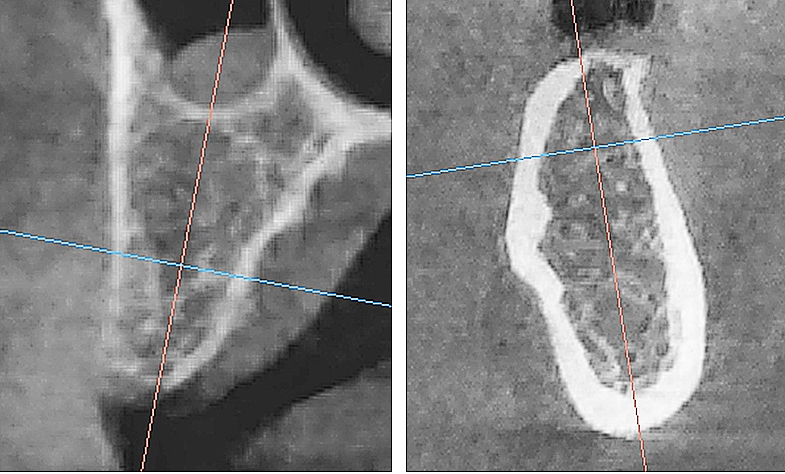

Рис. 2. Поперечный срез альвеолярной кости верхней челюсти человека в проекции отсутствующего премоляра (А) и альвеолярная кость нижней челюсти человека в проекции отсутствующего моляра (Б). 3D-КЛКТ

Учитывая выше перечисленные недостатки, поиск новых областей и способов хирургического доступа для создания экспериментальной модели исследования остеопластических материалов является актуальным. Нас заинтересовало использование в качестве экспериментальной живой модели область локтевого отростка передних конечностей овцы. В доступной литературе нами не встречено упоминаний об использовании локтевых отростков овец с целью формирования костных дефектов для оценки регенераторного потенциала остеопластических материалов. Вероятно, это обусловлено боязнью риска травматизма локтевого отростка в ходе формировании дефекта при использовании классического хирургического инструментария – сверл и фрез большого диаметра. Между тем очевиден ряд преимуществ данной области – схожее анатомическое строение и архитектоника с альвеолярной частью челюстей человека. Локтевой отросток имеет наружный кортикальный слой и внутренний, представленный губчатым веществом с костномозговыми пространствами небольшого размера (рис. 1, 2).

Рис. 7. Контрольная рентгенограмма локтевого отростка сразу после операции. Визуализируются 4 трепанационных отверстия, титановые пины, фиксирующие коллагеновую мембрану

После хирургического этапа проводили рентгенологический прицельный контроль в каждой области имплантации (рис. 7).